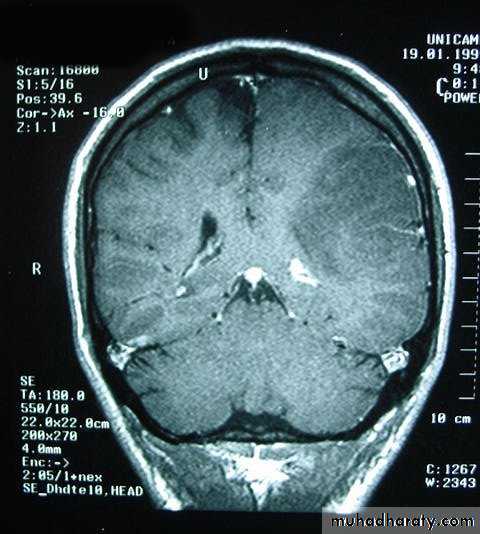

Metastatic Brain TumoursMRI